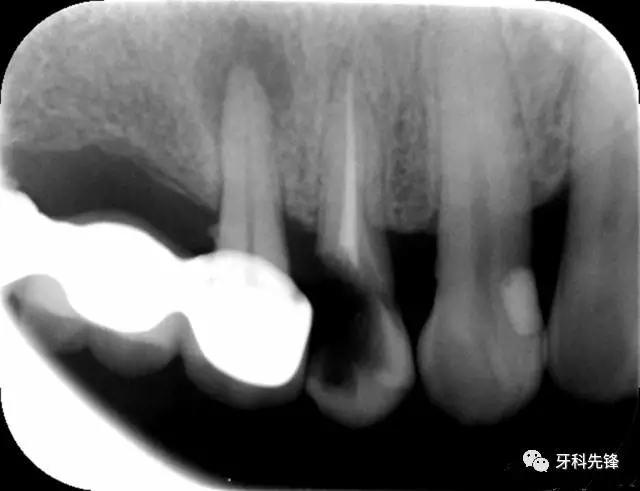

圖1 術(shù)前X光片

640.webp.jpg

640.webp (1).jpg

640.webp (2).jpg